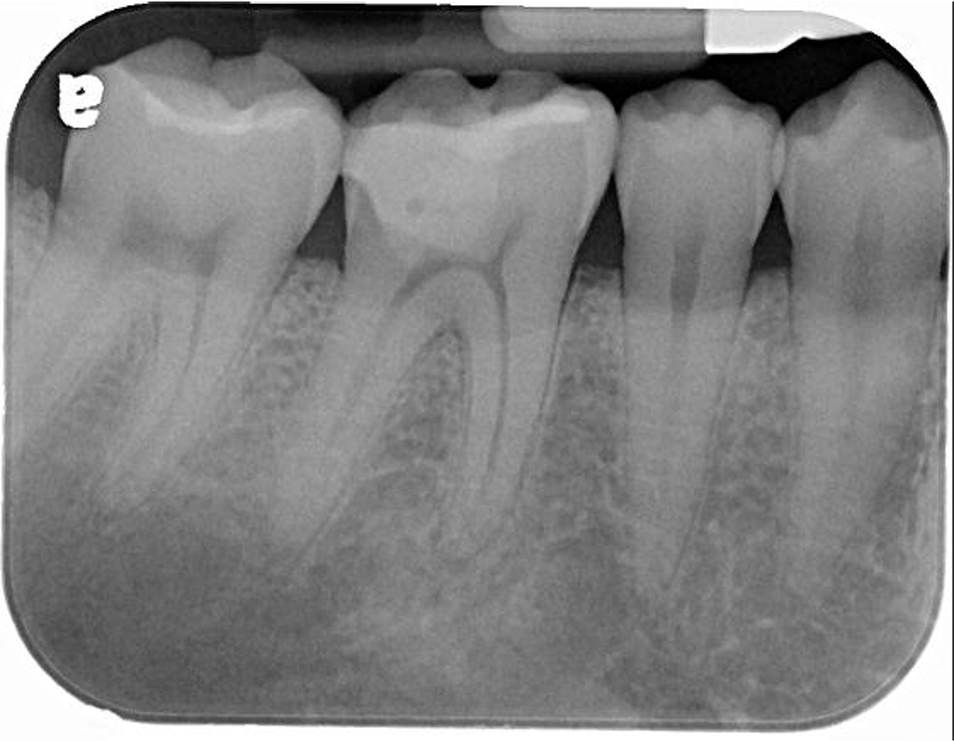

治療前,蛀牙與根尖破壞

先進行非手術顯微根管治療